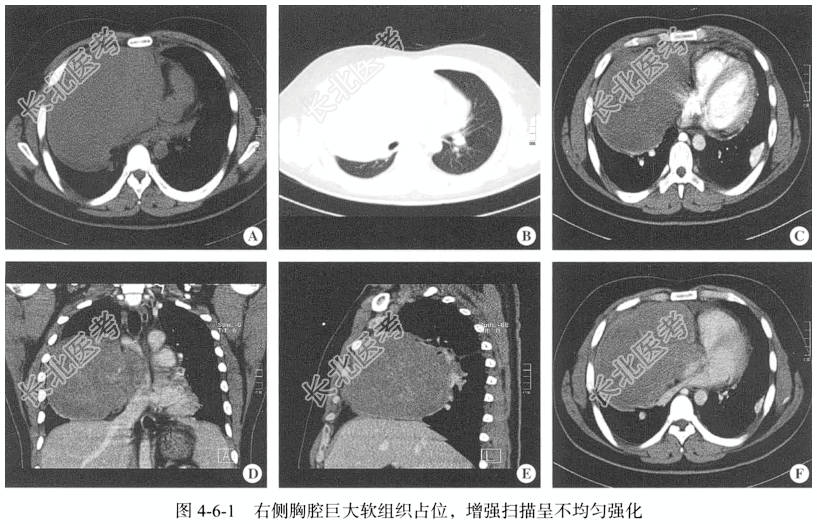

- [材料题] 【影像图片】见图4-6-1。

【病理所见】(右肺)条索组织4条,长0.5~1.2cm(图4-6-2)。免疫组化结果:PAS(-),CK(上皮+),Vim(+),SMA(间质+),Des(灶+),CAM5.2(上皮+),CD38(-),CD138(灶+),EMA(灶+),CEA(部分上皮+),CgA(-),S-100(灶+)。

【病理诊断】肺母细胞瘤。